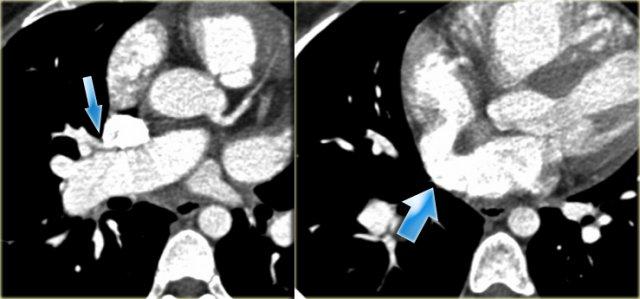

Double Arch with Atretic Segment

Occasionally the double arch can have an atretic segment.

You should not confuse it for a right arch.

The left arch is just very small and there is still a four vessel sign.

On the left a dominant right arch and a small left arch.

The atretic segment is marked by the arrow.

Notice the four vessel sign.

On a posterior view the interruption is nicely demonstrated.

Remember that there is still a ring, so there is still obstruction.

Another case on the left.

Do not call this a right arch.

It still is a double arch and there is a atretic fibrotic segment on the posterior side of the left arch, that completes the ring.

Same patient.

Always look at the airways.

On the recoonstruction the impression on the trachea is better appreciated.